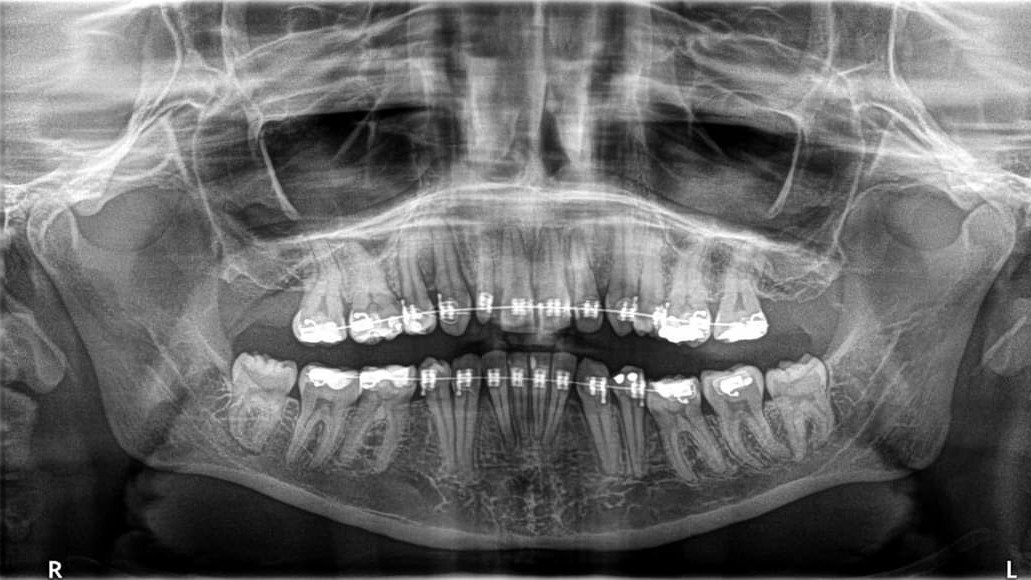

O prostych zębach marzyłam od zawsze. No ok - Odkąd wyrosły mi stałe zęby 😅 Na leczenie ortodontyczne mogłam sobie pozwolić finansowo mając prawie 28 lat. Usłyszałam od kilku osób, czy mi na stare lata się opłaca? 🤣 Stwierdziłam, że tak! Inwestycja poczyniona w swoją pewność siebie na pewno zaprocentuje! Odłożyłam pieniądze i z radością poszłam je zostawić u ortodonty. Bez chwili zawahania usunęłam 5 (dość ważnych jak się później okazało) zębów. Jedną ósemkę, dwie piątki, dwie czwórki. Wróżka Zębuszka nie przyszła, ale zostawiłam sobie je na pamiątkę 😁 Nie było mi to na tamtą chwilę straszne, zaufałam ortodoncie, sądząc że jego działania są słuszne. Chodziłam sumiennie na wizyty i czekałam na efekty. Czekałam. I czekałam..

Po dwóch latach i wydanych ponad 8 000 zł zaczęłam wątpić w wiedzę ortodonty i prawidłowość leczenia. Przypomniało mi się jak to jest wstydzić się mówić, śmiać, jeść.. Po wyrwanych zębach miałam (mam!) szpary, które nie chcą się zejść, zgryz jest nadal krzywy, mój uśmiech wygląda źle 😥

Wzięłam sprawę w swoje ręce, zrezygnowałam z usług dotychczasowego "specjalisty" i tu zaczął się mój problem. Bedąc na kilku wizytach u innych ortodontów dowiedziałam się, że żaden nie podejmie się dalszego leczenia. Że w sumie im przykro, że nie mogą pomóc, ale w zębach aktualnie jest za duży bałagan. Usłyszałam też coś, co mnie załamało - trzeba będzie zrobić implanty (gdzie dwa lata wcześniej za decyzją ortodonty usunęłam zdrowe zęby). I w tym momencie się rozpłakałam 🥺

Wrzucam kilka zdjęć. Niestety te, na których się uśmiecham jest garstka.